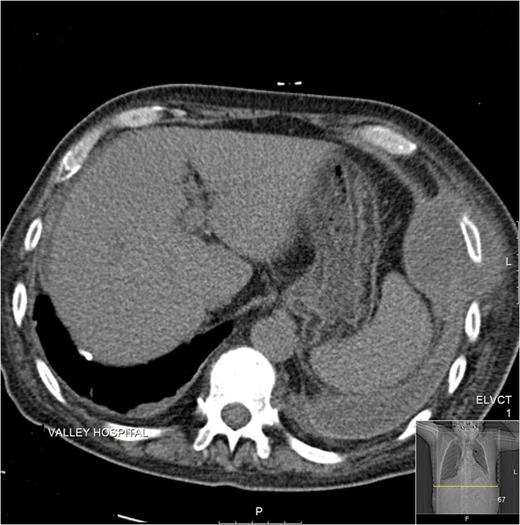

Subsequent high-resolution computed tomography (CT) chest demonstrated a well-defined lesion of 7.4 cm × 7.6 cm of reduced attenuation in the left lateral chest wall, encasing seventh and eighth ribs, without rib destruction (Fig. 1).

CT image demonstrating a well-defined chest-wall lesion encasing ribs, without rib destruction.